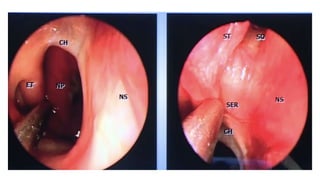

This document discusses the microanatomy of the sellar and suprasellar regions as well as operative approaches for accessing these areas. It describes the bones, venous connections, arterial relationships and incisura spaces in the regions. Several surgical approaches are mentioned, including sublabial, transseptal, endonasal, and subfrontal transfrontal transsphenoidal approaches. Key anatomical structures like the optic chiasm, carotid protuberance, cavernous sinus and clival indentation are located using an "owl eye" panoramic view of the fetal face mimicking centers.